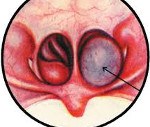

• Риноскопия. При классической передней риноскопии определяется отечность и гиперемия слизистых оболочек, наличие слизистых или слизисто-гнойных масс. Выполнение риноэндоскопии позволяет визуализировать в общем носовом ходу плотное образование бледно-серого или красноватого цвета.

• Мезофарингоскопия. При осмотре ротовой полости у больных с полипами больших размеров позади свободного края мягкого неба определяется нижний полюс плотного образования розоватого цвета.